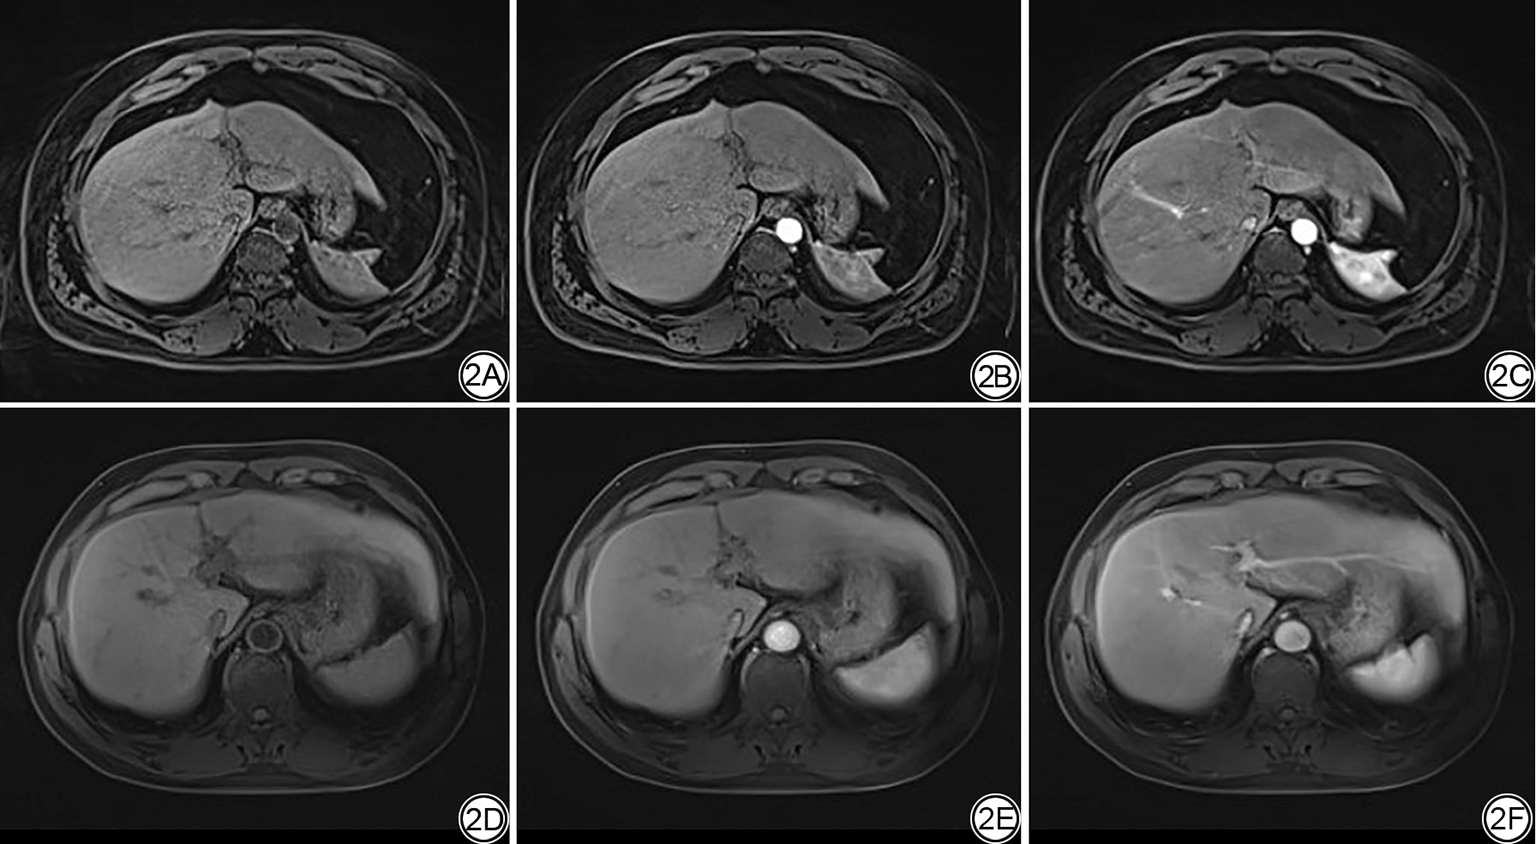

观察者间的主观评价一致性较好,Kappa值范围为0.65~0.78。CS-GRASP序列优化组中肝左、右叶图像噪声、条纹伪影、图像清晰度和整体图像质量得分均高于未优化组,差异有统计学意义(P<0.05),见表5图2

图2  肝门静脉左支水平对肝左、右叶噪声,条纹伪影,图像质量和肝脏结构清晰度方面图像主观评分。2A~2C:男,55岁,CS-GRASP未优化肝脏平扫图像,主观评分分别为平扫(2A)3、4、2、3、2分,动脉期(2B)3、4、3、3、2分,静脉期(2C)3、4、4、4、3分;2D~2F:男,54岁,CS-GRASP优化肝脏图像,主观评分分别为平扫(2D)4、5、5、4、4分,动脉期(2E)5、5、5、4、4分,静脉期(2F)5、5、5、5、5分。

Fig. 2  Subjective scoring of the images at the level of the left portal vein regarding the noise of the left and right liver lobes, radial artifacts, image quality, and clarity of liver structures. 2A-2C: A 55-year-old male patient with unoptimized GRASP liver images, with subjective scores of 3, 4, 2, 3, 2 for the plain scan (2A), 3, 4, 3, 3, 2 for the arterial phase (2B), and 3, 4, 4, 4, 3 for the venous phase (2C). 2D-2F: A 54-year-old male patient with optimized GRASP liver images, with subjective scores of 4, 5, 5, 4, 4 for the plain scan (2D), 5, 5, 5, 4, 4 for the arterial phase (2E), and 5, 5, 5, 5, 5 for the venous phase (2F).